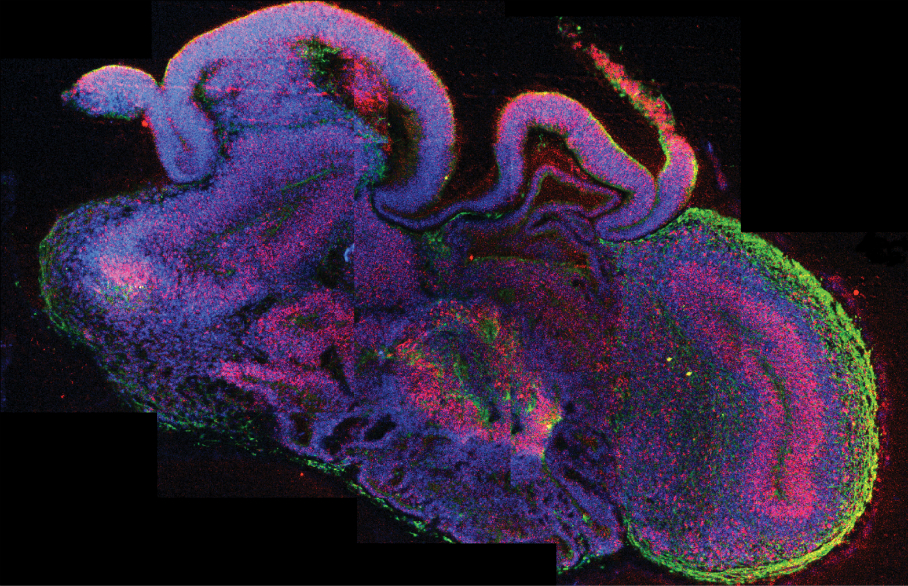

A 3-D model brain organoid with different brain regions. All cells show up blue, neural stem cells are red and neurons are green. Madeline A. Lancaster

The cerebral organoid, as its creators have dubbed it, resembles the early developing regions of a human brain, with distinct regions like the dorsal cortex, the ventral forebrain and even an immature retina. This is the most complex in vitro human brain tissue so far. It has the beginning signs of cortical layers, though it can’t develop the full complexity of a six-layer human cortex.

Though it looks very similar to early-development brain tissue and has active neurons, the organization isn’t quite the same as in naturally developing tissue. “The parts are correctly organized, but not put together,” Juergen Knoblich, who coordinated the study, explained in a press conference. He describes it as “a car where you have an engine, you have the wheels–but the engine is on the roof…that car would never drive, but you could still take that car and analyze how an engine works.”